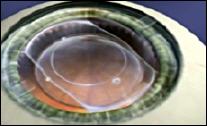

die ICL schwimmt auf der natürlichen Linse

Für hohe Kurzsichtigkeiten und dünne Hornhäute, bei denen eine Laserbehandlung nicht in Frage kommt gibt es die Möglichkeit der ICL, einer in die Vorderkammer des Auges zwischen die Iris und vor der natürlichen Linse eingepflanzten speziellen weichen Contactlinse. Auch Linsen, die in die Pupille eingesetzt werden, sog. Irisfixierte oder "Klauenlinsen" (Artisan, Verisyse Linse) werden hier angewandt.

hier eine ICL Hinterkammerlinse in ihrer Position - nach Pupillenverengung ist sie unsichtbar.